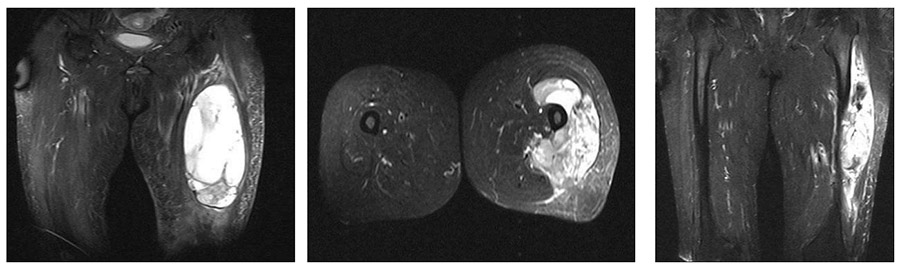

Ameliyat Öncesi: MR’da uyluk dış kısımda femuru 180 dereceden fazla sarmış düzensiz sınırlı heterojen kitle görülmekte